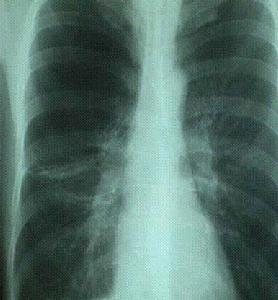

呼吸摔衰竭的發病環節呼吸衰竭是由於外呼吸功能障礙導致的結果。其發生機制包括:肺通氣障礙(限制性通氣不足、阻塞性通氣不足);肺換氣障礙(肺泡膜面積減少、肺泡膜厚度增加);通氣/血流比例失調(功能性分流、死腔樣通氣);解剖分流增加。呼吸衰竭時PaO2降低或伴有PaCO2升高,這些變化對機體各系統功能會產生重要影響,如發生肺性腦病及肺源性心臟病。